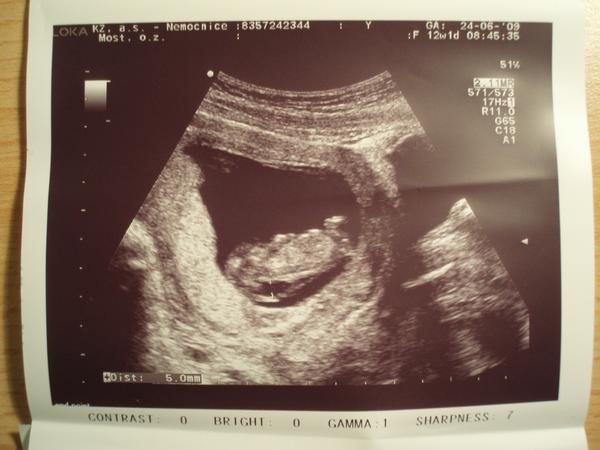

@ivcula7 ve 4 a 5 měsíci je mimčo už velké, to pak se dělá klasickým porodem. ALe nešil. Vždyt ještě nemáš nic potvrzené. 4etla jsi celou diskuzi? já jsem tu jeden čas sepisovala všechny výsledky. zkusím najít poslední soupis. Jo a hodím ti sem foto naší Adélky, kde je vidět jak měla prosáknutí v záhlaví, neboli velké šíjové projasnění, neboli NT. Ne jednom vidíš dole údaj dokonce 5mm. to je délkamezi těmi dvěma body na fotce, jak to doktor měřil. Něco takového viděl i u tebe, že?

@klara.t : NT 4,6, nosní kůstka přítomna, odběr chor.klků - genetika v pořádku, krev v pořádku, UTZ v 16. týdnu v pořádku, velký UTZ v 20.týdnu v pořádku - holčička , kardiologie-podezření na nedomykavost trojcípé chlopně, ale málo významné, na další kontole - srdíčko se umoudřilo, nedomykavost se sama spravila, UTZ v 31+1 v pořádku, 1.1. 2010 se narodila Adélka (3290g, 49cm) - zdravá a v pořádku, kontrola srdíčka - naprosto v pořádku

@lucida : NT 4,6 má zdravou holčičku

@olga777: NT=4,6 (12tt), UTZ OK

Mě tenkrát doktor říkal, že NT do 6 je v pohodě. Stejně mě neuklidnil a začala jsem pátrat na netu po informacích. A našla jsem tyto stránky a ponořila se do toho problému víc a víc (u dcery jsem ani nevěděla, že nějaké NT hodnoty existují a měla 3,5. A byl klid). U syna by mi doktor ani ty NT(4,6) hodnoty neřekl, kdybych se nezeptala. Tenkrát mě naštval a odešla jsem od něj 🙂